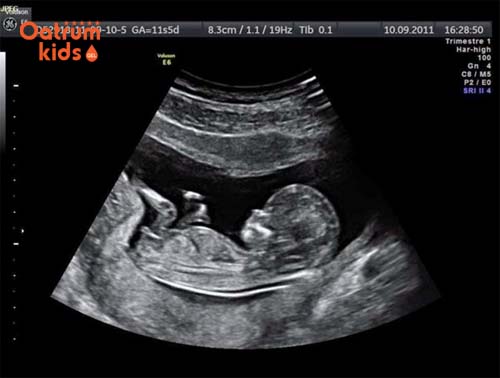

1.3. Cách tính tuổi thai theo siêu âm

Siêu âm là kĩ thuật được sử dụng phổ biến nhất hiện nay, cho phép chẩn đoán thai sớm và chắc chắn, nhất là siêu âm với đầu dò âm đạo thường giúp nhìn thấy túi thai sớm khi 5 tuần tuổi (một tuần sau khi chậm kinh). Đa số các trường hợp, siêu âm bụng có thể xác định được tình trạng có thai trong tử cung kể từ khi thai được 6 tuần tuổi. Vì vậy, cách tính tuổi thai theo siêu âm vừa thuận tiện, an toàn, phổ biến và có độ chính xác cao. Với siêu âm ta có thể thấy:

- Túi thai, từ tuần lễ thứ 4-5 sau khi tắt kinh. - Cấu trúc phôi từ tuần lễ thứ 6-7. - Tim thai từ tuần lễ thứ 7-8. - Hoạt động thai từ tuần lễ thứ 9. - Trước tuần lễ thứ 14, với siêu âm đo chiều dài đầu mông là phương pháp tốt nhất để dự đoán tuổi thai (sai lệch 4 ngày). - Tuổi thai có thể được ước lượng bằng một số cách đo lường thông dụng sau:

- Tuổi thai (số ngày) = đường kính trung bình của túi thai + 30.

- Tuổi thai (số ngày)= kích thước phôi + 36.

- Sau tuần thứ 14, muốn tính tuổi thai nhi chính xác nhất cần đo đường kính lưỡng đỉnh..

Cách tính tuổi thai dựa vào hình ảnh siêu âm